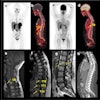

Cases of the Week

Check out our Cases of the Week!